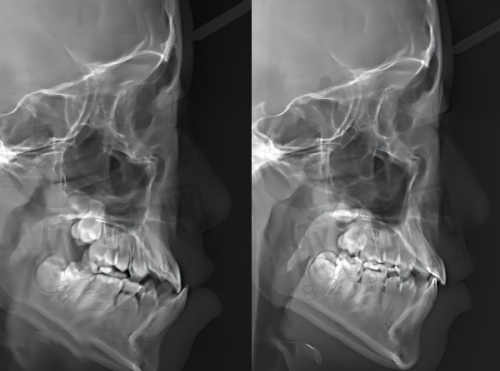

(3)医生可靠:给患者看诊的罗文清医生非常专精,从开始的拍片到确定方案,都以专精负责的态度详细地告知患者各方面情况,让患者觉得来广州柏德口腔矫正十分靠谱,特别期待矫正后的成效。